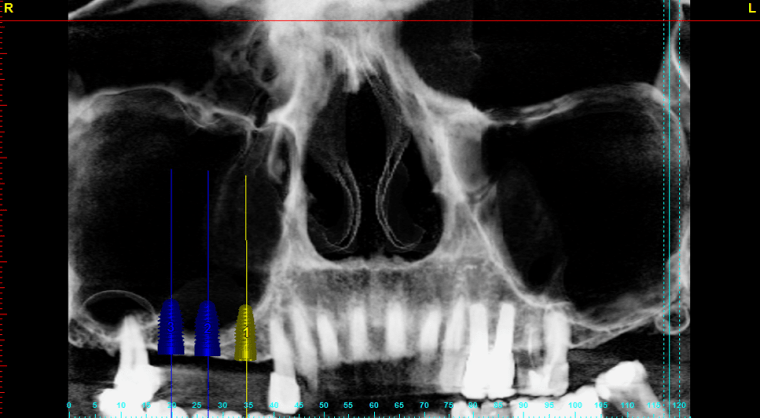

In this site I’ll be posting random dental snip its. In this case, we used this timeline for a recent sinus lift. I’ve never done one just participating with the faculty on this one. This is the timeline we went in with. It actually took much longer. Leave any comments below about what you may do differently or any thoughts about the procedure.